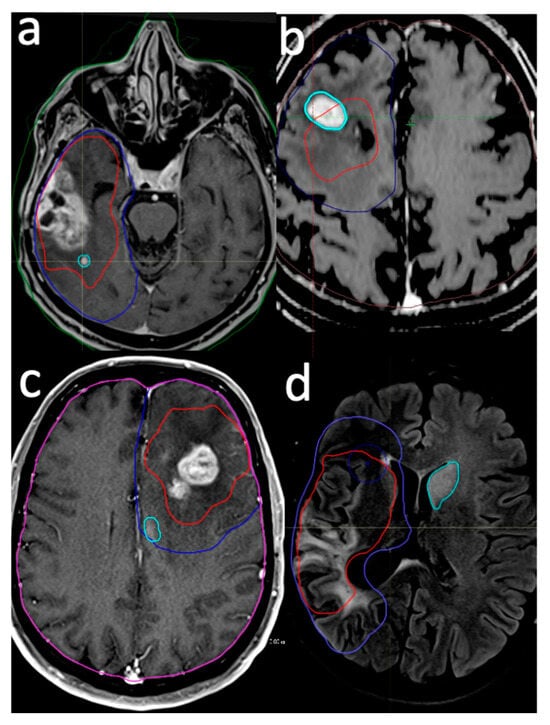

2.2. Target Delineation and Systemic Treatment

2.3. Delineation of Failure Pattern

- Intra-GTV: Recurrence is either entirely contained within the original GTV or originates within the GTV and extends beyond its boundaries.

- In-CTV/out-GTV: Recurrence occurs within the CTV but does not have any contact with the GTV, indicating that it is completely outside the GTV but still within the CTV.

- Distant: Recurrence is situated beyond the confines of the radiation field, signifying that the tumor has recurred at a location not encompassed within the original treatment area.

- Intra-GTV and distant: Recurrence is present both within the GTV and at a distant site outside the radiation field, implying multiple areas of tumor regrowth.